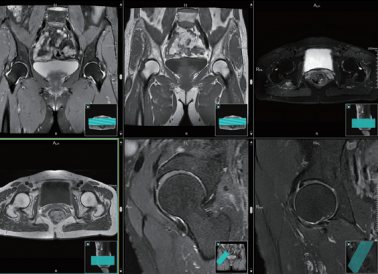

原理先容:MRI检查因奇异的软组织成像与区分功效,可为临床检查有用提供冠状面、横断面和矢状面等差别平面的图像,能高敏感性地区分出软骨、骨、枢纽囊及肌肉等组织。髋枢纽MRI可详细形貌髋白周围软骨、骼腰肌、髋枢纽Y型软骨、髋臼内圆韧带和枢纽囊等周围软组织形态

临床用途:1. 股骨头缺血坏死、骨坏死、髋臼盂唇损伤; 2. 可清晰显示枢纽积液、髋白内脂肪增生等征象是否保存; 3. 小儿化脓性髋枢纽炎的股骨头受累情形小儿髋枢纽发育不良